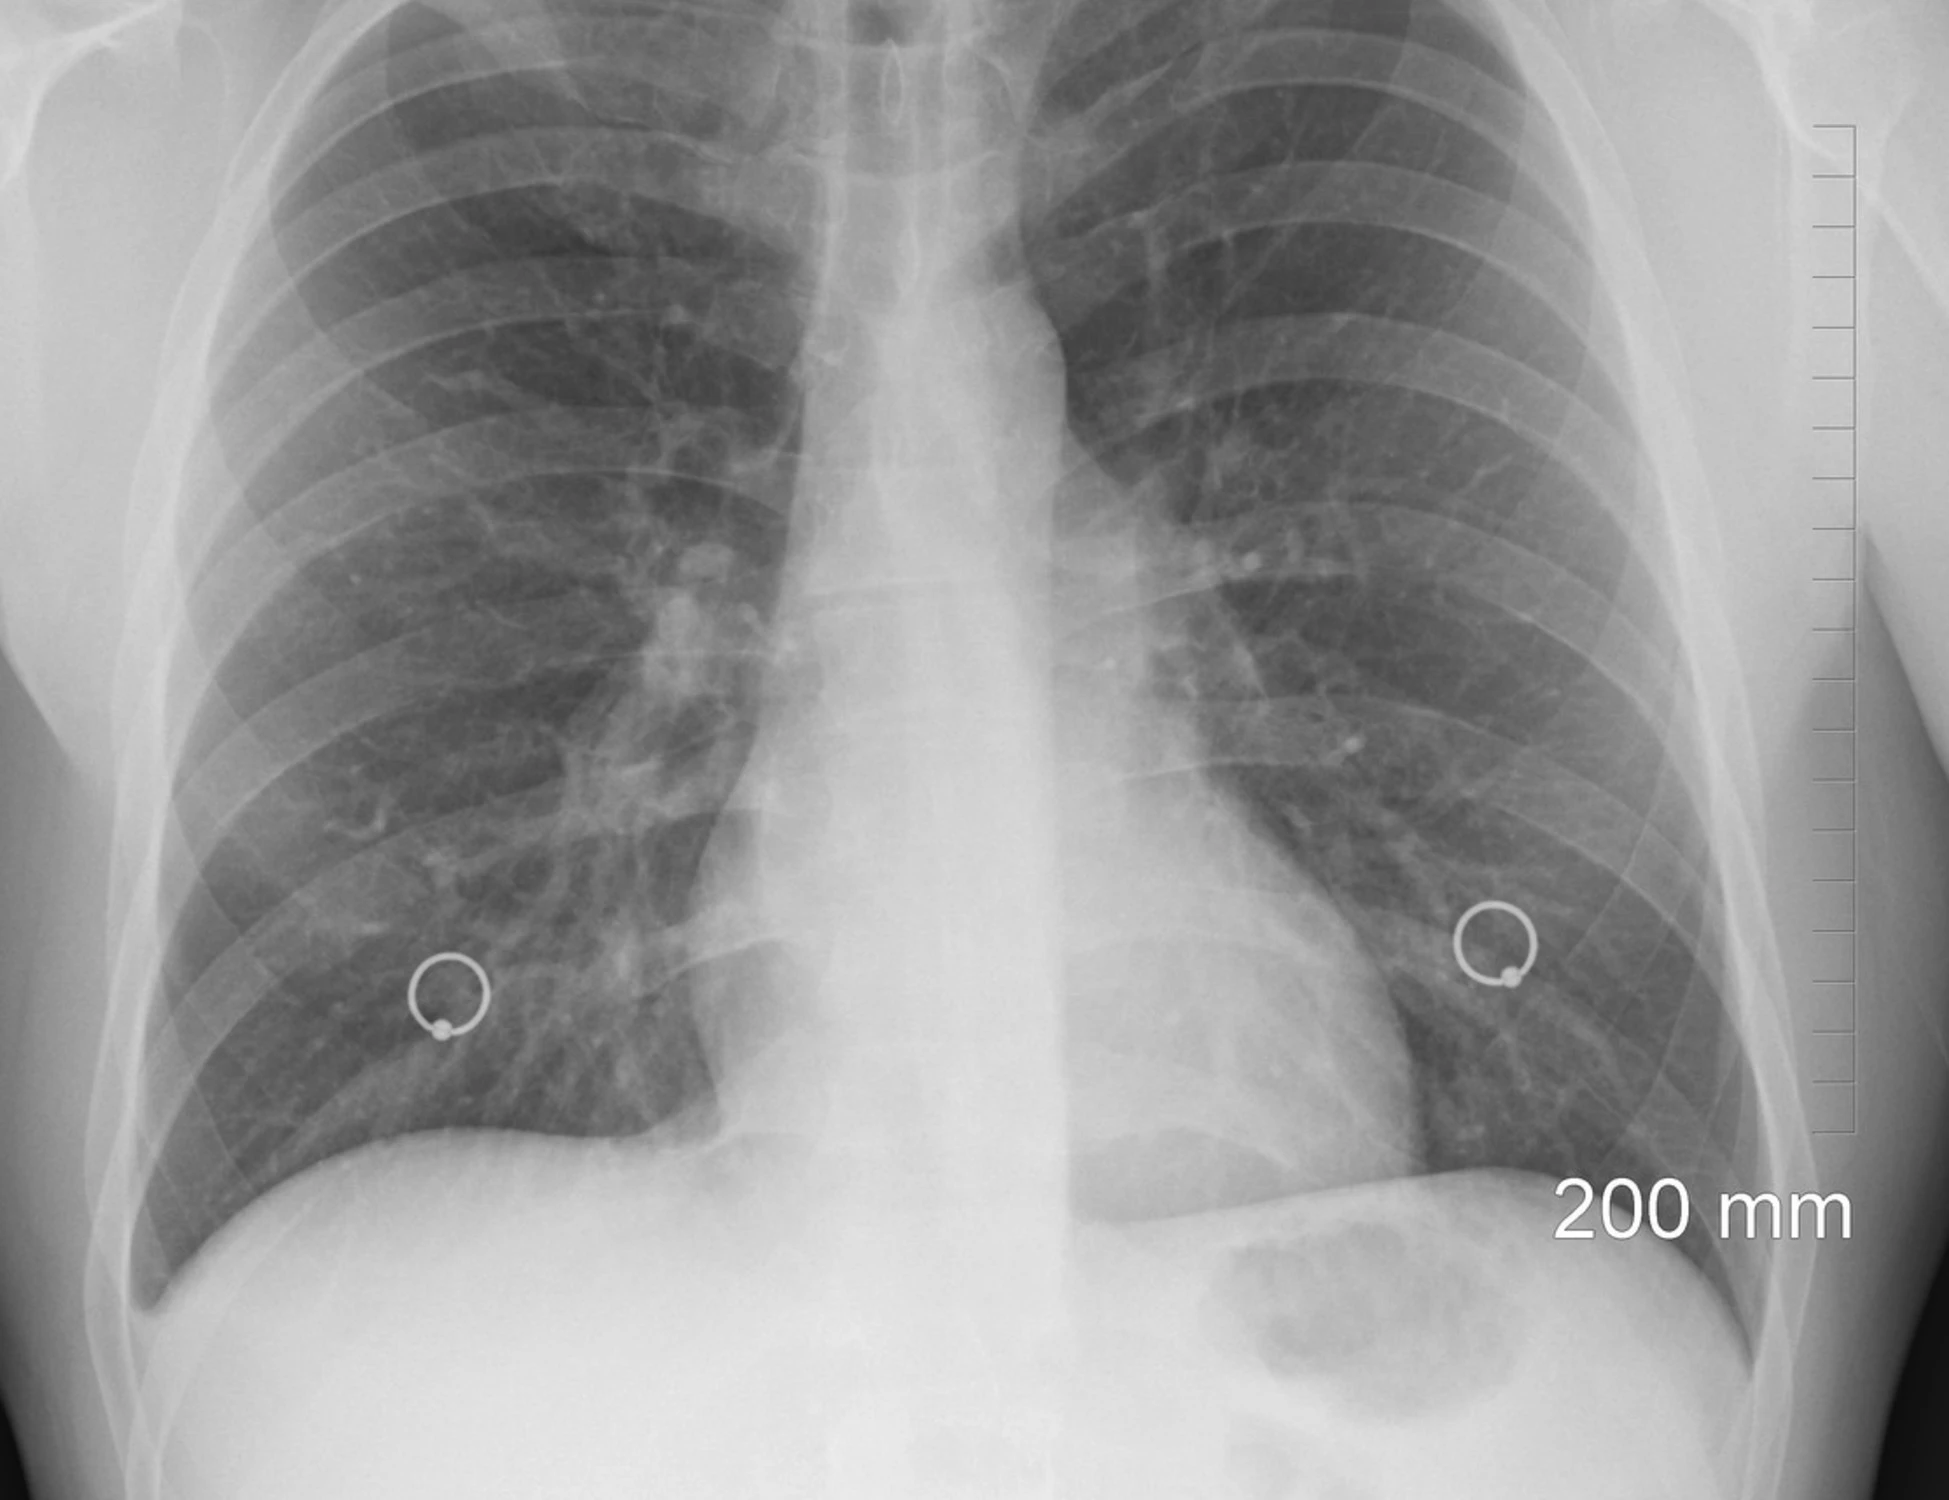

Tumore, come curarlo senza danni al cuore: la ricerca